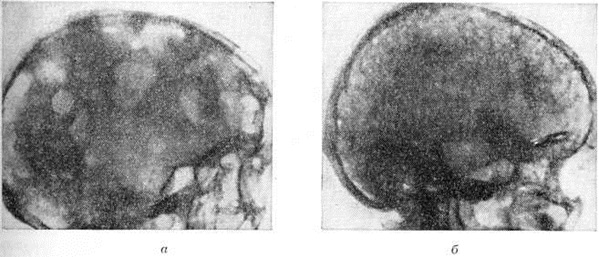

Рис. 11.

Рентгенограммы черепа при миеломной болезни; боковая проекция: а — множественные чётко очерченные («пробойниковые») очаги деструкции; б — мелкоочаговые изменения в костях черепа.